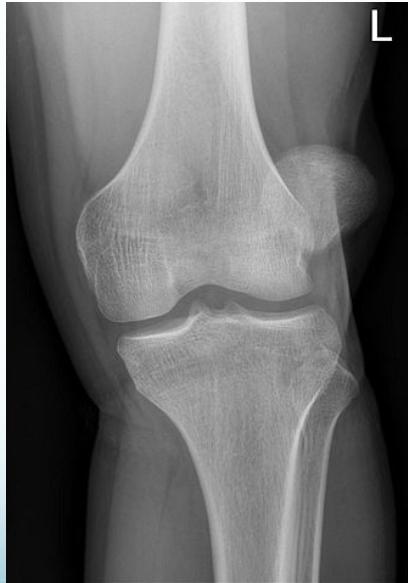

X-rays: Standard knee radiographs

X-ray Findings:

- Dislocation

- Fractured tibial spine (cruciate ligament avulsion)

- Avulsion fibular styloid (collateral ligament avulsion)